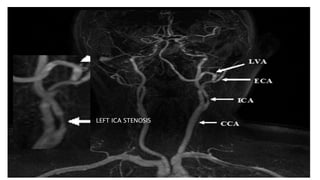

2D TOF MIP MRA 3D TOF VRT MRA

BILATERAL CAROTID MRA TOF MIP

LEFT ICA STENOSIS

• #63 Here is TOF MIP and VRT MRA showing excellent angiogram due to background suppression and better flow related signal leading to better distal small vessel visibilty

• #64 here is an example of AP VIEW of normal MR angiogram of cervicocranial arterial system

• #65 In this MR angiography of bilateral carotid system there is e/o short segment narrowing of Left ICA s/o left ICA stenosis